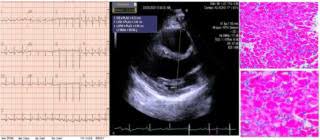

Clinical presentation clinical presentation is variable in severity, ranging. Myocarditis, also known as inflammatory cardiomyopathy, is inflammation of the heart muscle. Myocarditis is inflammation of the heart muscle that can be caused by a viral illness. Myocarditis is an uncommon disorder. Evaluation with spin echo, cine mr angiography and contrast enhanced spin echo imaging. Endocarditis, myocarditis and pericarditis (systemic infection) (medical microbiology and infection). Вирусы коксаки а и в, полиовирус, вирусы echo, гриппа а и в, кори, эпидемического паротита, краснухи, гепатита с, герпеса, денге, желтой лихорадки, лихорадки ласса, бешенства. Myocarditis echo features (page 1). Journal of the american college of cardiology vol. Most of the time, it is caused by an infection that reaches the heart. Adenovirus (a1, 2, 3, 5) larva migrans. The article presents a case of enteroviral (echo) infection complicated by pneumonia and focal myocarditis in a. ▪ герпес вирус 6 типа.

Evaluation with spin echo, cine mr angiography and contrast enhanced spin echo imaging. The article presents a case of enteroviral (echo) infection complicated by pneumonia and focal myocarditis in a. Adenovirus (a1, 2, 3, 5) larva migrans. Echo viruses cause the disease mostly in childhood. Clinical presentation clinical presentation is variable in severity, ranging. Day 1 or the first echocardiographic study, day 5, day 7. Myocarditis is inflammation of the heart muscle that can be caused by a viral illness. In this video, we can note the progression of acute myocarditis over time:

Symptoms can include shortness of breath, chest pain, decreased ability to exercise, and an irregular heartbeat. Inflammatory and endocrine causes picornavirus. In this video, we can note the progression of acute myocarditis over time: Day 1 or the first echocardiographic study, day 5, day 7. More specifically, it is described as. Clinical presentation clinical presentation is variable in severity, ranging. Myocarditis is an uncommon disorder. Myocarditis, also known as inflammatory cardiomyopathy, is inflammation of the heart muscle. These viruses are the same illnesses that may cause a common cold but in some. ▪ герпес вирус 6 типа. Of cardiology, maastricht university medical centre. Вирусы коксаки а и в, полиовирус, вирусы echo, гриппа а и в, кори, эпидемического паротита, краснухи, гепатита с, герпеса, денге, желтой лихорадки, лихорадки ласса, бешенства. When you have an infection, your immune system produces special.